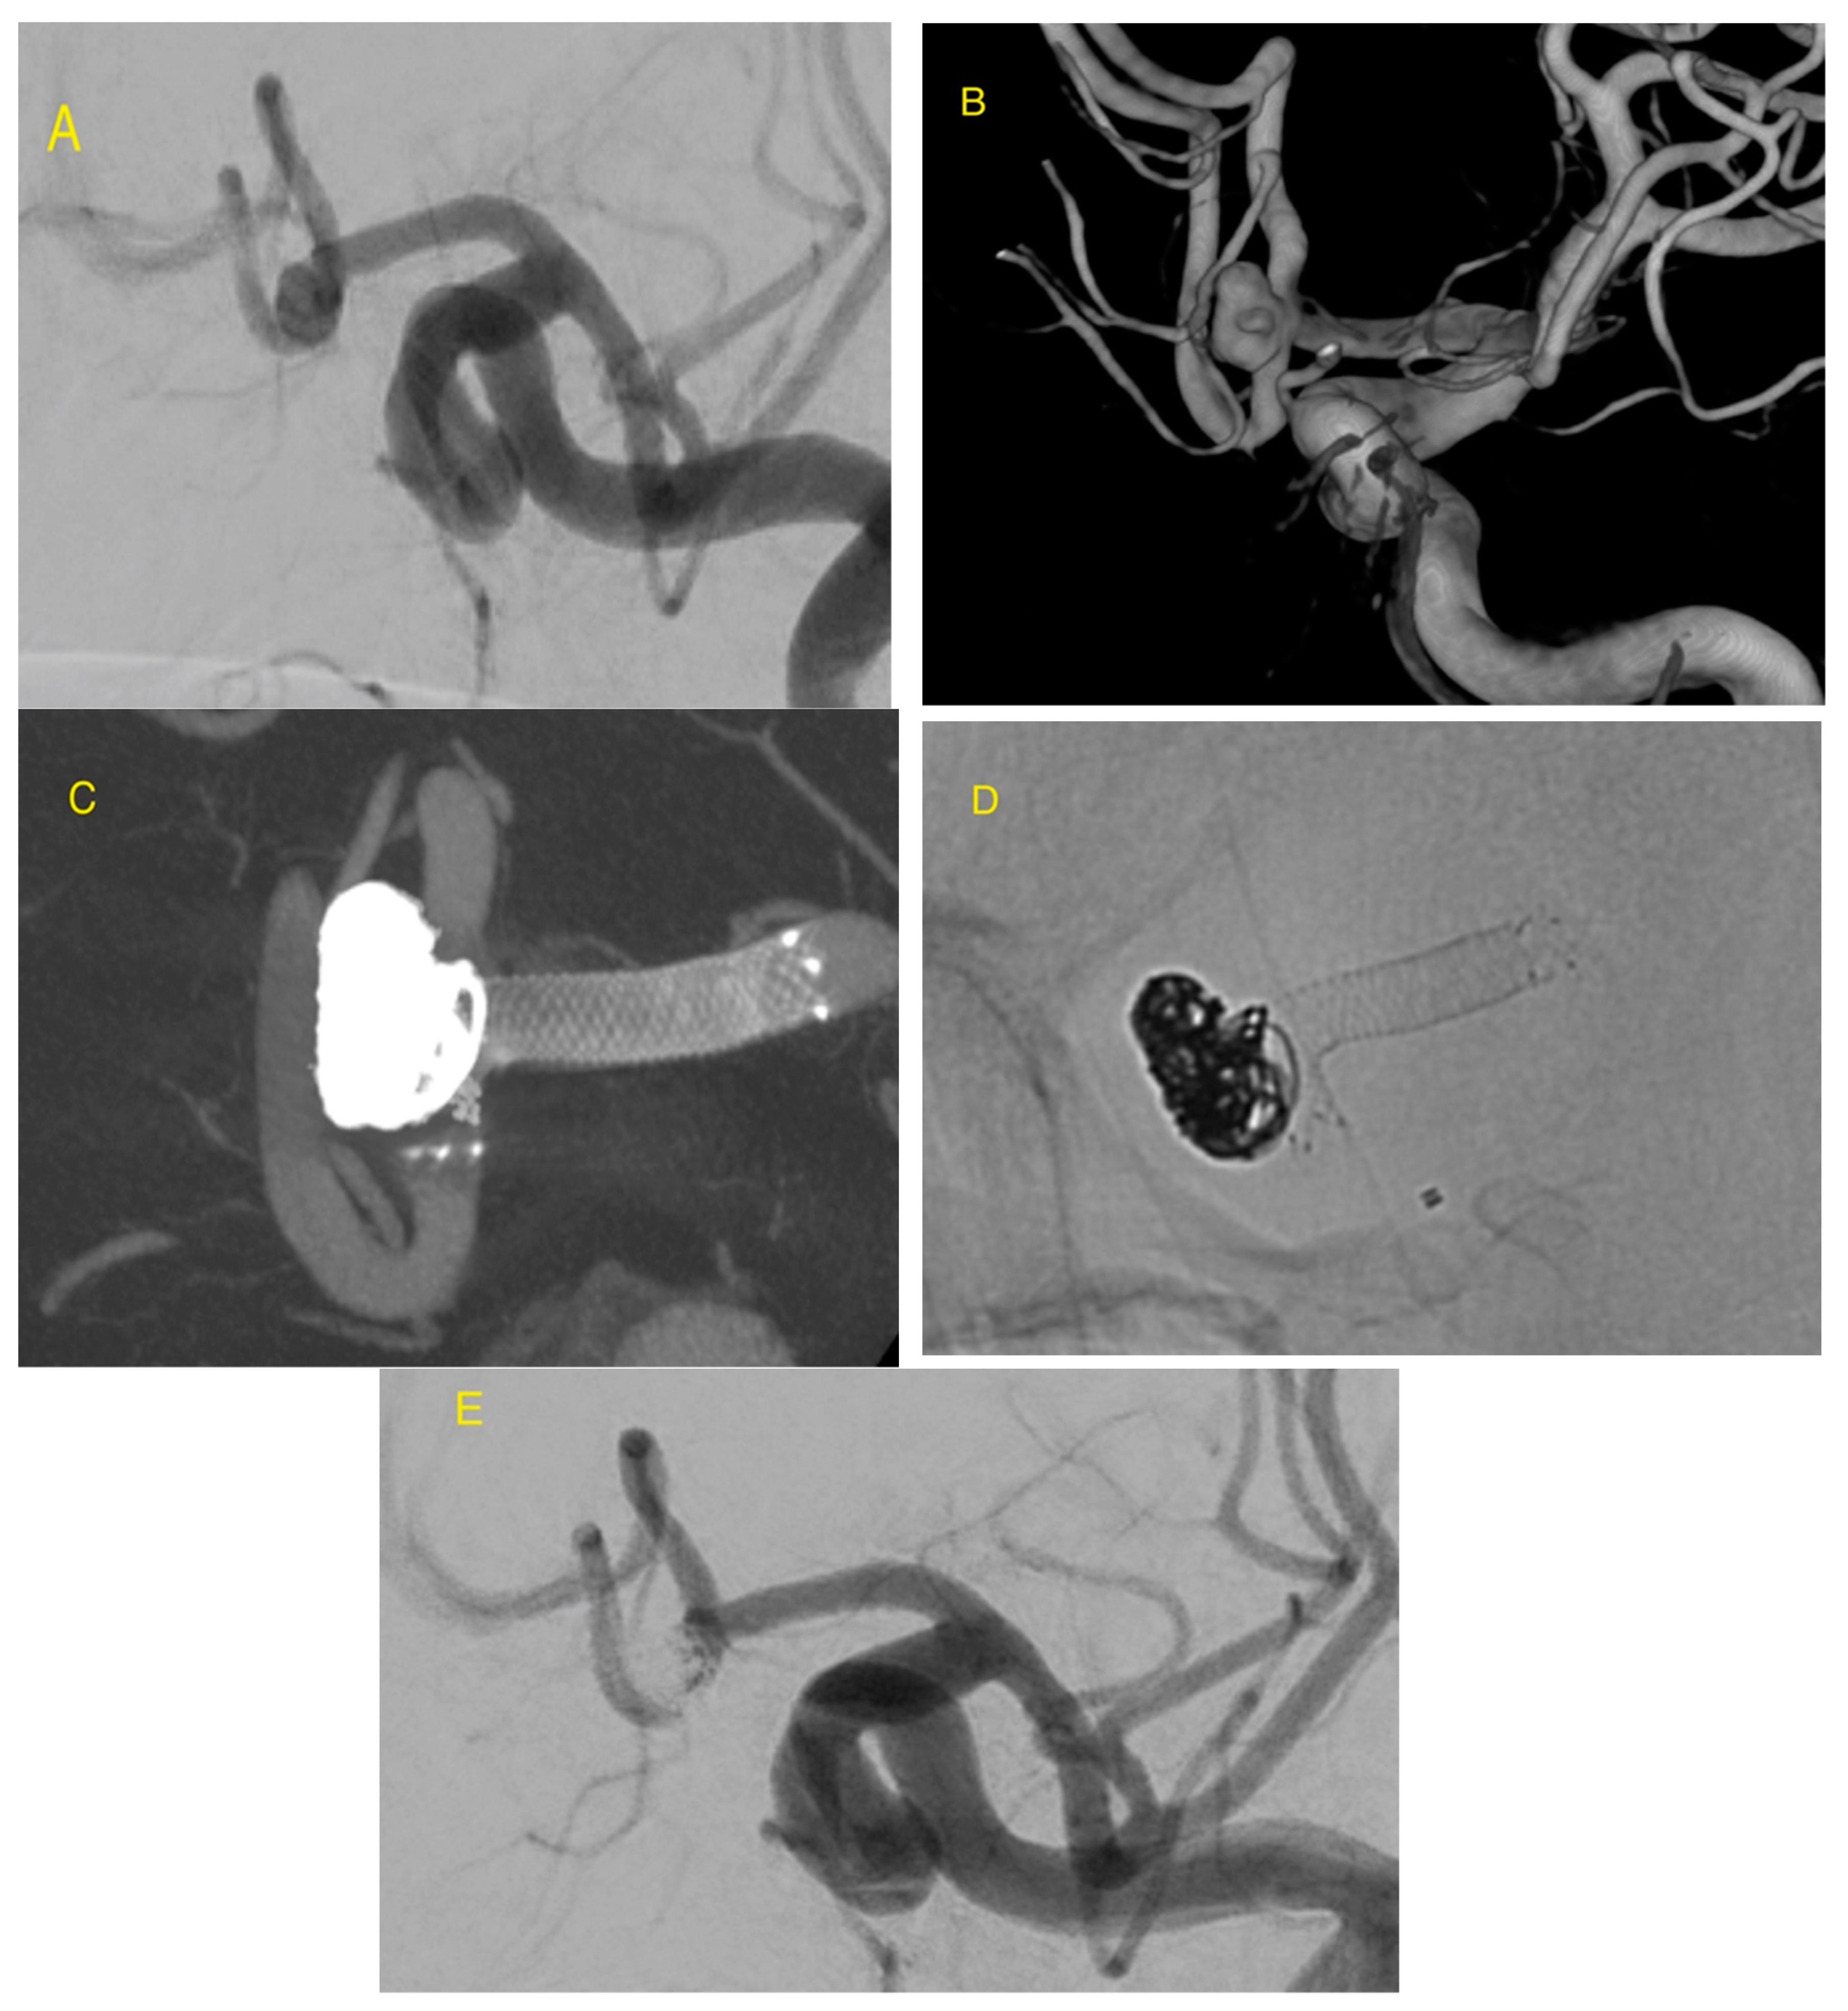

Initial Experience with LVIS EVO Stents for the Treatment of Intracranial Aneurysms

- Sirakov, A.; Bhogal, P.; Möhlenbruch, M.; Sirakov, S.S. Endovascular treatment of patients with intracranial aneurysms: Feasibility and successful employment of a new low profile visible intraluminal support (LVIS) EVO stent. Neuroradiol. J. 2020, 33, 377–385. [Google Scholar] [CrossRef]